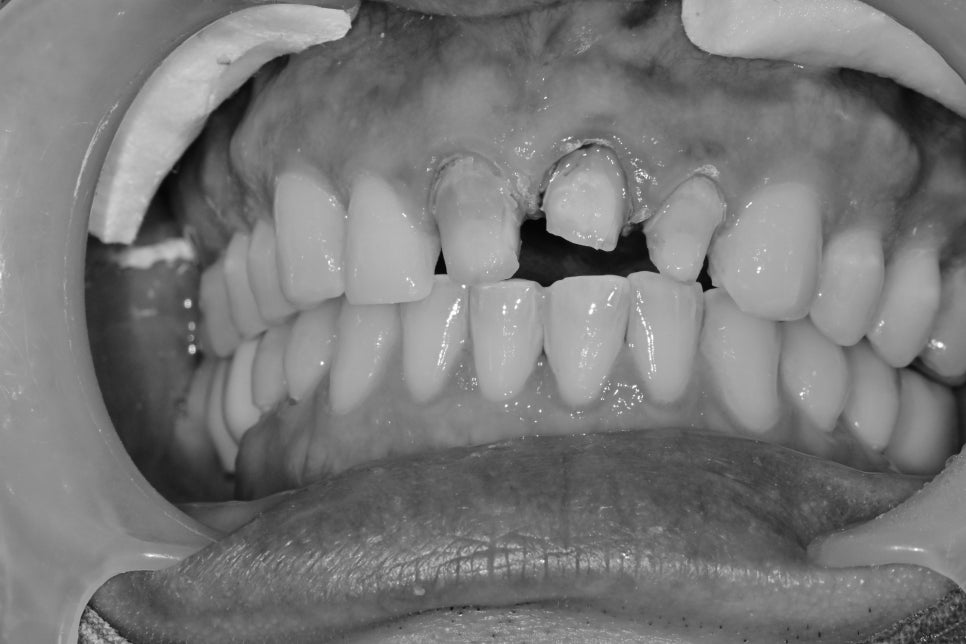

오래된 앞니 크라운이 색이 안 맞고, 경계 부분이 노출되었습니다.

과거에 치열이 바르지 않은 곳에

충치가 생겨서 신경치료를 했는데

치아배열을 올바르게 하기 위해

주변 치아를 같이 신경치료 후 심미보철 치료를 한 케이스입니다.

시간이 오래 지나다 보니 잇몸 쪽 보철의 경계 부위가 노출되고

주변 치아와 색상이 맞지 않았습니다.

재제작을 위해 보철물 3개를 제거했습니다.

이 경우 보철물의 유지를 높이기 위해 2개, 1개씩 묶어서 제작되었습니다.